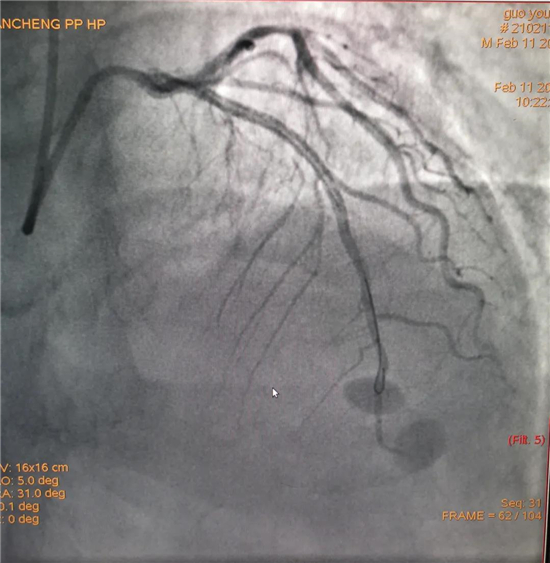

除夕,郭先生無(wú)明顯誘因突發(fā)胸痛,120急救人員到達(dá)現(xiàn)場(chǎng),心電圖顯示:竇性心律完全性束支傳導(dǎo)阻滯。信息立刻發(fā)送到胸痛中心介入微信群中,心內(nèi)科值班醫(yī)生初步診斷為急性廣泛前壁心肌梗死,必須盡快進(jìn)行急診支架治療,開(kāi)通血管。值班醫(yī)生電話(huà)指導(dǎo)院前治療,并立即啟動(dòng)胸痛綠色通道,24小時(shí)備班的介入治療團(tuán)隊(duì)立即到位,9:30患者被送到導(dǎo)管室行冠脈介入診療,9:40急診PCI手術(shù)隨之開(kāi)始,冠脈造影檢查提示左前降支閉塞,植入支架,堵塞的血管被順利打通,患者癥狀緩解,手術(shù)非常成功,10:20患者被送往病房進(jìn)一步治療。